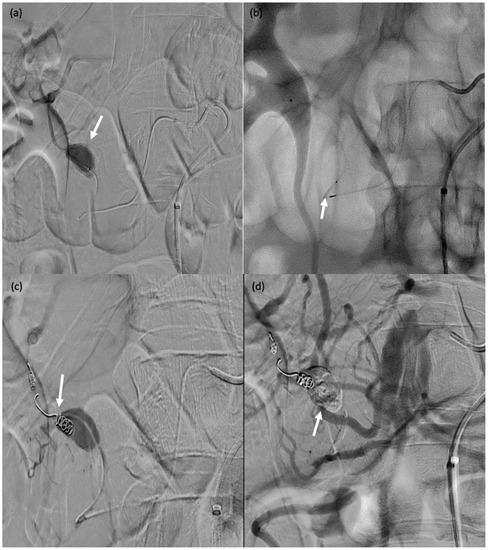

Figure 7. A 71-year-old male (patient #11) with abdominal pain and haemodynamic instability. (a) Rupture of a false aneurysm of the posterior pancreaticoduodenal arcade (arrow). (b) Failure of initial catheterisation for MVP-3Q implantation due to angulation of the target artery (arrow). (c) Coil embolisation of the downstream branch (arrow). (d) Onyx™ embolisation of the aneurysmal sac and upstream branch (arrow).